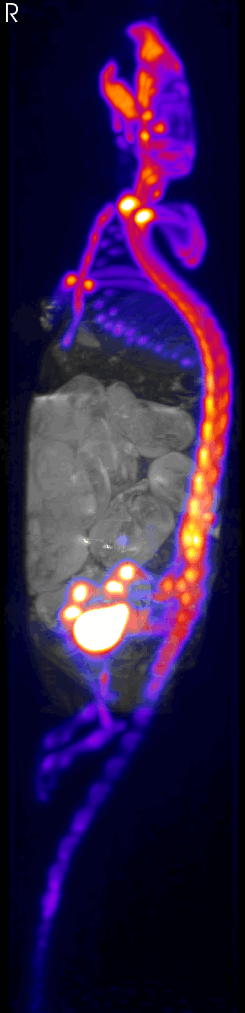

The PET Technology

FDG distribution

PET images living systems by recording high-energy γ-rays emitted from within the subject. The source of the radiation comes from positron-emitting-bound biological molecules, such as 18F-FDG (fludeoxyglucose), which is injected into the test subject. As the radioisotopes decay, they emit positrons which annihilates with electrons found naturally in the body. This produces 2 γ-rays at ~180° apart, which are picked up by sensors on opposite ends of the PET machine. This allows individual emission events to be localized within the body, and the data set is reconstructed to produce images.

The MRS-7000 system allows simultaneous PET/MR imaging, and can image whole body mouse and rat heads.